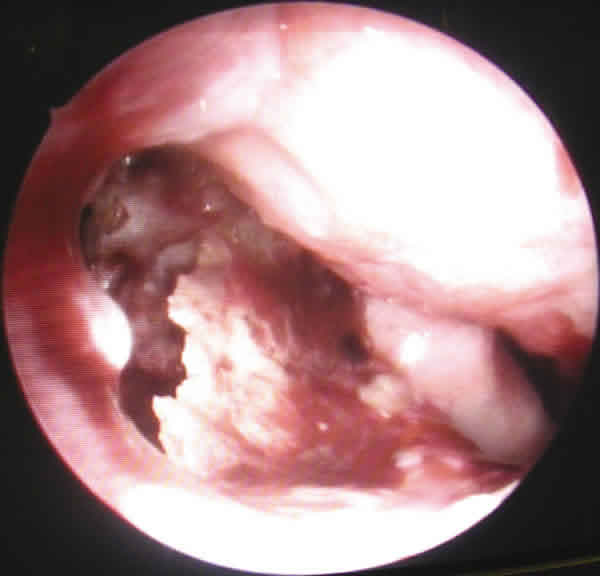

Fig. 2. Visión endoscópica de erosión hueso nasal.